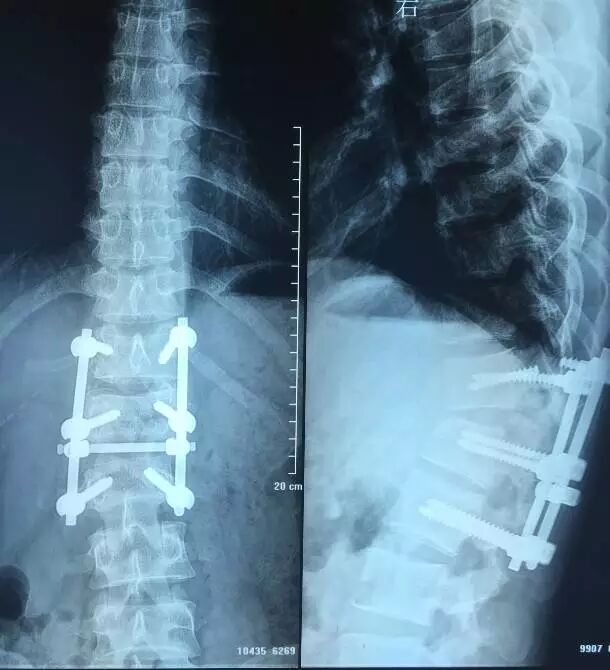

脊柱创伤、脊柱疾病、脊柱退变、脊髓损伤、脊髓疾病等典型病例,包括疑难病例、成功病例、尤其欢迎失败病例投稿。